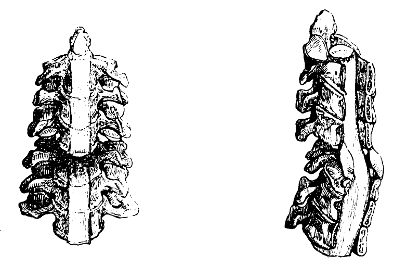

| Fractures of theSpinal Column | 560 |